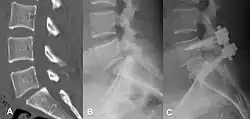

(A) Vista sagital de CT de un deslizamiento de bajo grado.

(B) Intervención preoperatoria de radiografía lateral.

(C) Tratado quirúrgicamente con descompresión L5 – S1, fusión instrumentada y colocación de un injerto intersomático entre L5 y S1.